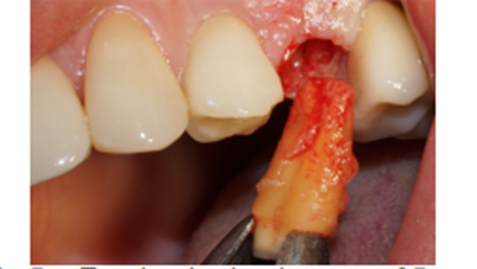

Paciente do sexo feminino, com viagem marcada para o exterior, apresentou-se em minha clínica com o diagnóstico de lesão e grande mobilidade do elemento 25. Após a solicitação dos exames preliminares e da anamnese, foi realizada a conduta medicamentosa e a cirurgia foi marcada para instalação imediata do implante (Figuras 3 e 4).

Foi eleito um implante Veloce Cone Morse de 3.75 X 11.5 mm e após a exodontia, o implante foi instalado utilizando o protocolo de fresagem recomendado pelo fabricante, fazendo uso das fresas escalonadas do sistema, alcançando um torque de inserção de 70 Ncm, o que me incentivou a promover o carregamento imediato deste implante (Figuras 5, 6, 7, 8, 9 e 10).